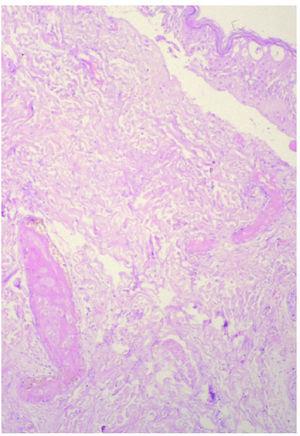

En los casos con larga evolución (> 6 meses), se llega a formar un pseudoquiste en el tejido celular subcutáneo que delimita en área de necrosis por extravasación. En este caso pudimos ver una gruesa pseudocápsula fibrosa envolviendo el tejido celular subcutáneo, que mostraba imágenes de necrosis por coagulación (fig. 7).

Fig. 7.--Gruesa pseudocápsula fibrosa que envuelve el tejido celular subcutáneo. (Hematoxilina-eosina, ×4.)

En las fases avanzadas (primer mes tras la extravasación) se encuentra fibrosis septal, ulceración epidérmica y necrosis de adipocitos con degeneración lipomembranosa de la grasa. En las fases tardías (varios meses después de la extravasación) pueden llegarse a formar pseudoquistes de necrosis grasa con fibrosis perilesional.